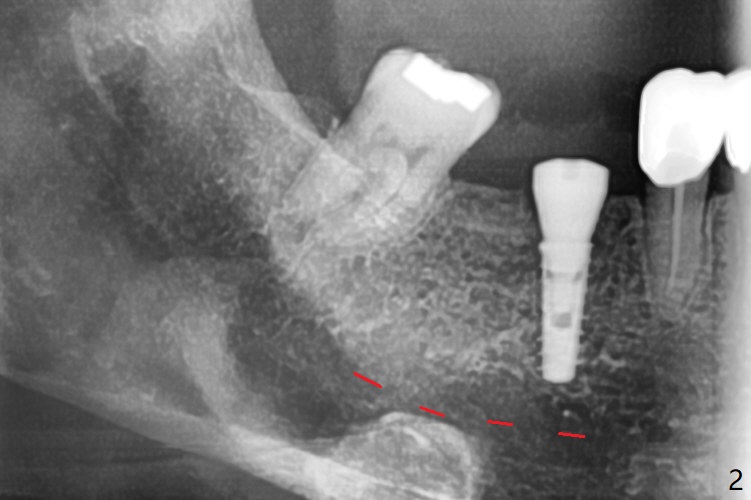

Since the preop ridge looks narrow at #30, incision is made, which makes it easy for observation of osteotomy. First, a 10.5 mm bone trimmer makes a deep dimple with apparently moderate ridge wide enough for a 4 mm implant. The patient has hypertension and cannot lie down for long. The bone density feels not high; a 4x11 mm (instead of 9 mm) implant is placed for 10 mm osteotomy (Fig.1 (~ 35 Ncm)). After use of 6 mm bone profile drill, there is bone buccal (less) and lingual to the implant. A 5.5x4 mm healing abutment is inserted, barely supragingival. As the implant is 1 mm longer than the design, regional panoramic X-ray is taken to determine clearance from the Inferior Alveolar Canal (Fig.2 red dashed line (the upper border). There is crestal bone loss 4 months postop (Fig.3,4). It appears that the implant was placed excessively deep. There is no implant thread exposure 9 months post cementation (Fig.5,6).